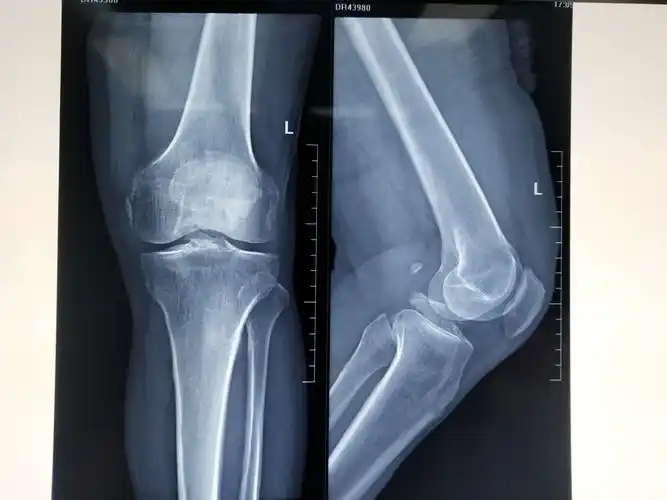

关节镜下单骨道单对纽扣钢板固定治疗大块胫骨髁间嵴骨折